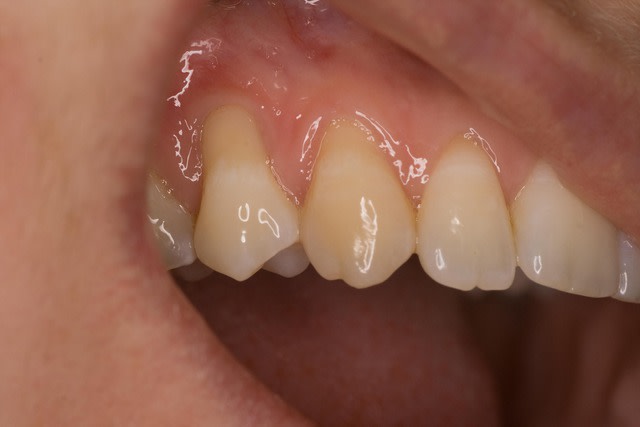

Voici un cas similaire, encore une 23, perte de tissu plus grande, pas de point suspendu avec compo, seulement 2 "sling-suture".

Greffon tracté sous lambeau en mésial et distal comme le cas précédent avec sutures.

Pas d'incision vertical en mésial, surtout que la 22 est un implant, placé trop apical, donc risque de perdre papille distal de 22 +++. Petite incision vertical en distal de 23, pour tracter le lambeau.

Photo final à 4 mois, belle intégration du tissu je pense.

Ça fait plus de 10 ans que je fais du conjonctif enfoui, et ça reste stable.

Si vous regardez le 2e cas, on voir des traces de papier bleu, la fonction canine a été modifié.

Saviez vous que bcp de dents présentes des déhissence osseuse vestibulaire sans pour autant avoir de poche paro ou de perte d'attache ? La présence d'os en vestibulaire n'est pas obligatoire, dans la mesure où l'os interdentaire est présent, pour avoir une gencive adéquate.